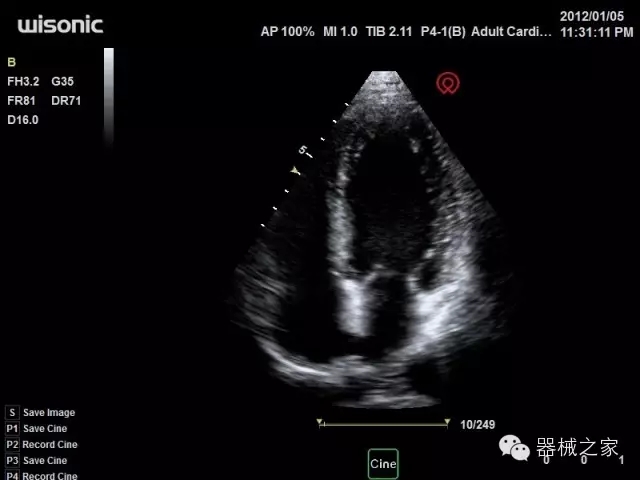

品牌:華聲醫(yī)療(WISONIC)

深圳華聲醫(yī)療技術(shù)有限公司成立于2012年,位于深圳南山西麗湖畔。是一家從事醫(yī)療設(shè)備研發(fā)、制造、營(yíng)銷的新興高新技術(shù)企業(yè),目前提供生命信息支持、數(shù)字便攜彩超、移動(dòng)醫(yī)療服務(wù)三個(gè)方面的業(yè)務(wù)解決方案。公司核心創(chuàng)始人均為醫(yī)療設(shè)備行業(yè)領(lǐng)軍人物,在醫(yī)療行業(yè)服務(wù)時(shí)間平均在10年以上,對(duì)行業(yè)和產(chǎn)品積累了深刻的認(rèn)識(shí)。公司在創(chuàng)立之初就有著長(zhǎng)遠(yuǎn)的戰(zhàn)略目標(biāo)和規(guī)劃,致力于醫(yī)療設(shè)備行業(yè)的細(xì)分市場(chǎng),貼近客戶所需,為大眾的健康提供更多關(guān)愛(ài)。

經(jīng)典產(chǎn)品:四葉草

臨床圖片賞析